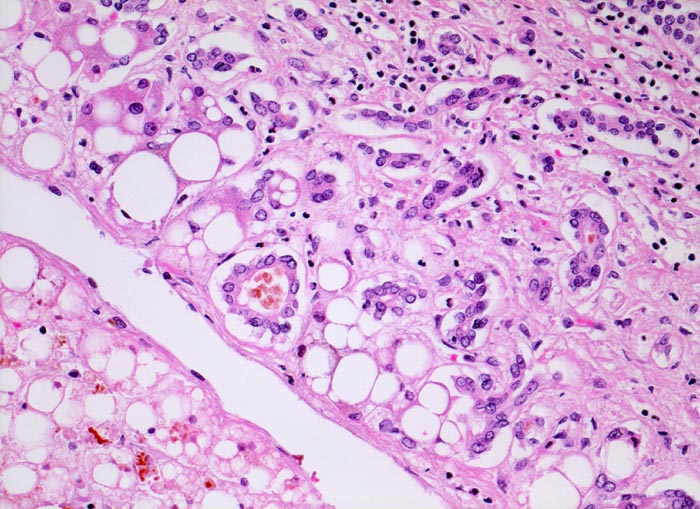

• Floride sklerosierende alkoholische Steatohepatitis: Grobtropfige Verfettung von ca. 50% des Parenchyms.Neutrophile Granulozyten umgeben einzelne Hepatozyten (Satellitose). Wenig Apoptosekörperchen. Zahlreiche Mallory Körperchen und Megamitochondrien. Perivenuläre Maschendrahtfibrose.

• Hydropische Schwellung periportaler Hepatozyten.

• Canaliculäre Cholestase in einem Zirrhoseknoten.